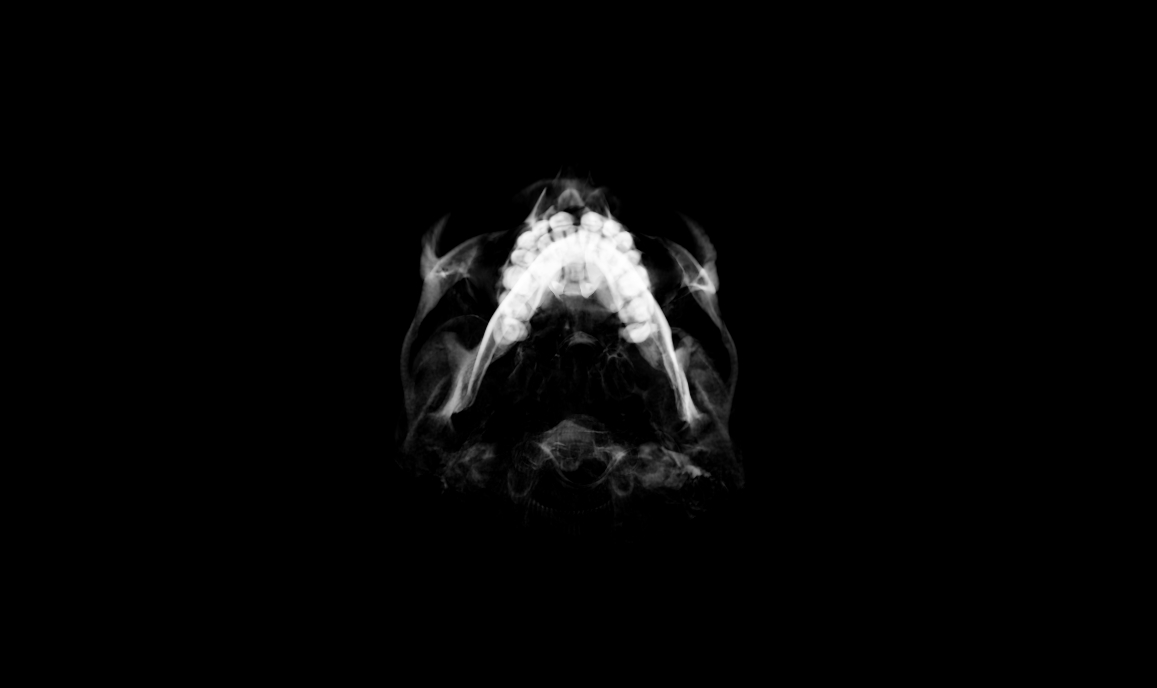

CBCT:

Note – I’m using 3D Slicer and couldn’t figure out a setting that showed the bone nicely with this one. Possibly because the metal of the expander is much denser so it skews the range. Please send me an email/comment if you know how to get it to render well. I don’t need detail on the expander.